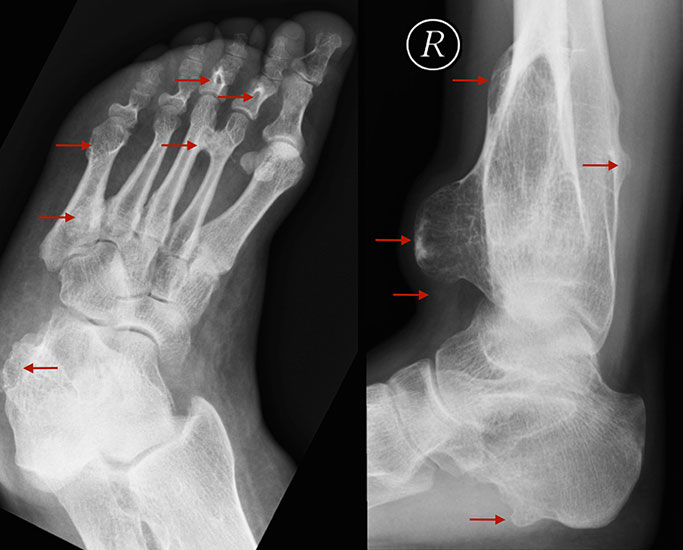

Axiale CT-Aufnahmen eines Osteoidosteoms im Bereich des Calcaneus mit typischer Nidusbildung und perifokaler Sklerose (links). Bildgesteuerte Thermofrequenzablation der Läsion (rechts).

Die klinischen Symptome von Knochentumoren sind bis auf wenige Ausnahmen sehr unspezifisch. Schmerzen, Schwel­lung und Bewegungseinschränkungen können auch von zahllosen anderen krankhaften Prozessen ausgehen, insofern sind dementsprechende anamnestische Angaben nur zum Teil weiterführend. Knochenschmerzen zählen zu den somatischen Schmerzen und werden im Gegensatz zu neurogenen oder viszeralen Schmerzen meist als dumpf oder ziehend beschrieben. Neben der Qualität des Schmerzes kann aber auch die Intensität und das zeitliche Auftreten im Tagesverlauf hilfreiche Informationen liefern. Nachtschmerzen und ein positiver Aspirintest können beispielsweise konkrete Hinweise auf das Vorliegen eines Osteodiosteoms (Abb. 6) bieten. Der zeitliche Verlauf der beklagten Symptome kann Rückschlüsse auf das biologische Verhalten zulassen. So wachsen gutartige Tumoren in der Regel deutlich langsamer als aggressive, bösartige Neubildungen. Ausnahmen der Regel, so wie das Synovialsarkom, können jedoch falsche Sicherheit vortäuschen.

Die Computertomographie (CT) wird seltener als die MRT herangezogen um eine spezi­fischen Artdiagnose zu finden, liefert aber wertvolle Informationen zur Kortikalis­beschaffen­heit (Kontinuität, Stärke, enostale Arrosion) unterschiedlichster Knochenläsionen. Insbe­sondere die enostale Kortikalisarrosion, wie sie häufig bei chondrogenen Tumoren anzu­treffen ist, kann konkrete Hinweise liefern, die in Zusammenschau mit histologischen Befunden zu einer definitiven Diagnose führen (siehe Spezifische Entitäten: Enchondrom vs. atypischer chondrogener Tumor/Chondrosarkom). Die Computertomographie ist außerdem hilfreich in der Abgrenzung komplexer anatomischer Strukturen (z.B. 3D-Rekonstruktion) und sehr kleiner Knochenläsionen. Bei der Diagnose des Osteoidosteoms bleibt die CT Mittel der Wahl um die charakteristischen Veränderungen in der bildgebenden Diagnostik exakt darzustellen (Abb. 6). Die Gewebedichte von weichteiligen Tumoren, insbesondere von intra- und extraossären Lipomen, kann im Vergleich zum subkutanen Fettgewebe mithilfe der Houndsfield-Skala beurteilt werden.